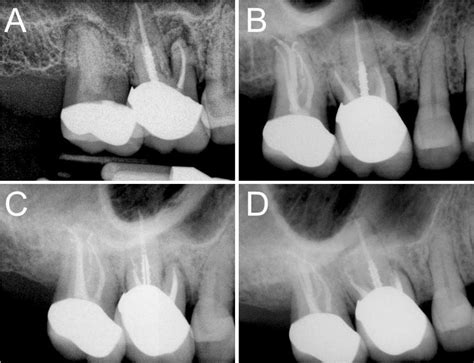

1. Diagnosis and Anesthesia: Your dentist will take X-rays to assess the extent of the infection. Local anesthesia is administered to ensure you do not feel pain during the treatment.

3. Cleaning and Shaping: The infected pulp is carefully removed using specialized dental instruments. The canals are then cleaned, disinfected, and shaped to receive a filling material.

4. Filling and Sealing: The hollowed-out canals are filled with a biocompatible material called gutta-percha, which is cemented into place.

5. Restoration: Because a tooth that has undergone an Rct of teeth may become brittle, a crown or permanent filling is usually placed to protect it and restore its original functionality.